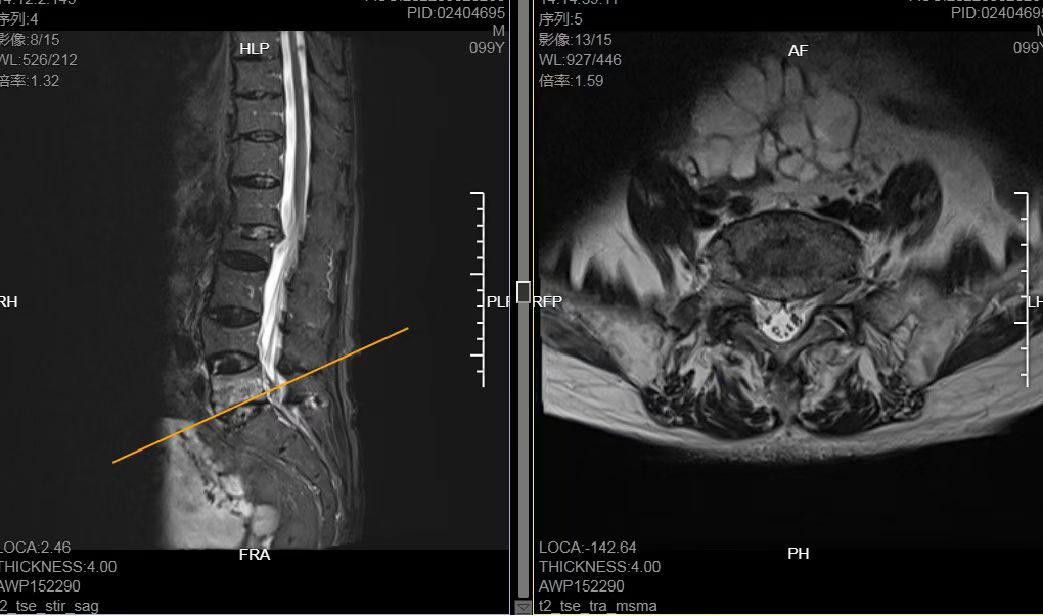

一年前,袁老先生曾经因为左侧股骨转子间骨折在我院骨科做过闭合复位髓内针内固定手术治疗,术后恢复良好,下肢功能完全恢复,因此,患者及家属对我院骨科的技术和服务有着切身体会。此次看到保守治疗无效,3月3日,家属主动联系到骨科蔡兆鹏副主任医师。蔡医生经过仔细体格检查并结合影像学资料,诊断为腰椎体新鲜性压缩骨折。

对这位一年里两度“光临”的高龄患者,蔡兆鹏副主任医师十分熟悉:老人家年轻时是一名矿工,常年的矿山作业使他罹患了矽肺职业病,有肺部阻塞性通气功能障碍,常年咳痰喘。此次,患者已经卧床一个月之久,极易出现多种并发症,后果不堪设想。为此,蔡兆鹏医生建议及时早行腰5椎体经皮椎体成形术治疗。患者家属表示完全服从专家建议。

鉴于正值深圳抗疫形势最为严峻的时期,根据医院防控工作的严格要求,医院立即开启“绿色通道”,第一时间为老人家核酸采样、检测,阴性结果出来后,立即为老人办理入院手续。入院当天,蔡兆鹏副主任医师将病情汇报给著名骨科专家、院长沈慧勇教授。沈慧勇教授立即查看病人,组织科内病情讨论,制定相应手术方案,并行精准的术前规划。仅用大半天时间,袁老先生就完成了心脏、双肺、下肢血管等多项术前必须检查。

入院第二天,即3月4日,沈慧勇教授团队即在基础麻醉下行腰5经皮椎体成形术。由于患者严重骨质疏松,注入椎体内的骨水泥容易泄露,手术难度较一般患者大了许多,但是手术团队在沈慧勇教授带领下,每一个手术操作都有条不紊、配合流畅,进展顺利。从手术操作开始至结束,用时仅30分钟,全程出血不到2毫升。

术后次日,复查术后X片,提示骨水泥位置良好。沈慧勇教授带领管床医师蔡兆鹏副主任医师查房,指导患者进行功能锻炼,并协助患者于胸背部支具保护下行走。